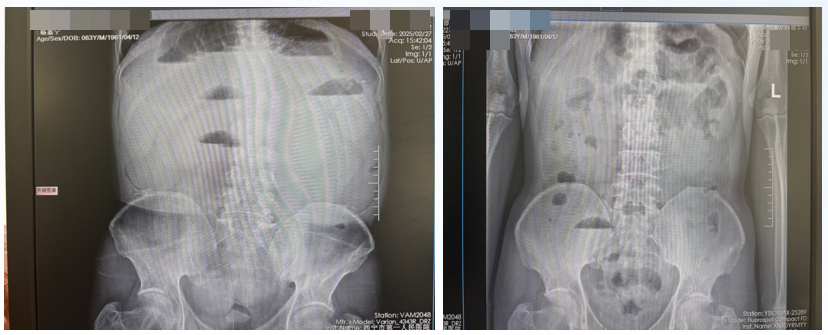

患者于2025-03-19完善腹部及盆腔CT示:吻合口未见明显异常强化征象,胃窦部胃壁增厚,建议胃镜检查。右肾囊肿。两侧肾上腺皮质增生并右侧肾上腺内支小腺瘤可能。前列腺增生伴钙化(图2)。

图2. 腹部CT检查(2025-03-19)